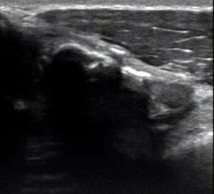

La fracture du sternum est assez rare, cet os étant protégé par les côtes et leurs cartilages qui jouent un rôle d'amortisseurs élastiques et qui sont lésés en priorité.

Cependant on peut noter des fractures directes du sternum lors de chocs sur la partie antérieure du thorax (le cas de notre rugbyman) ou plus rarement indirectes après une chute sur le dos ou le siège

Le fait qu'il n'y ait pas eu de traumatisme franc ne devra pas, dans ce cas de figure, nous faire oublier de passer la sonde sur les 3 constituants de cet os...